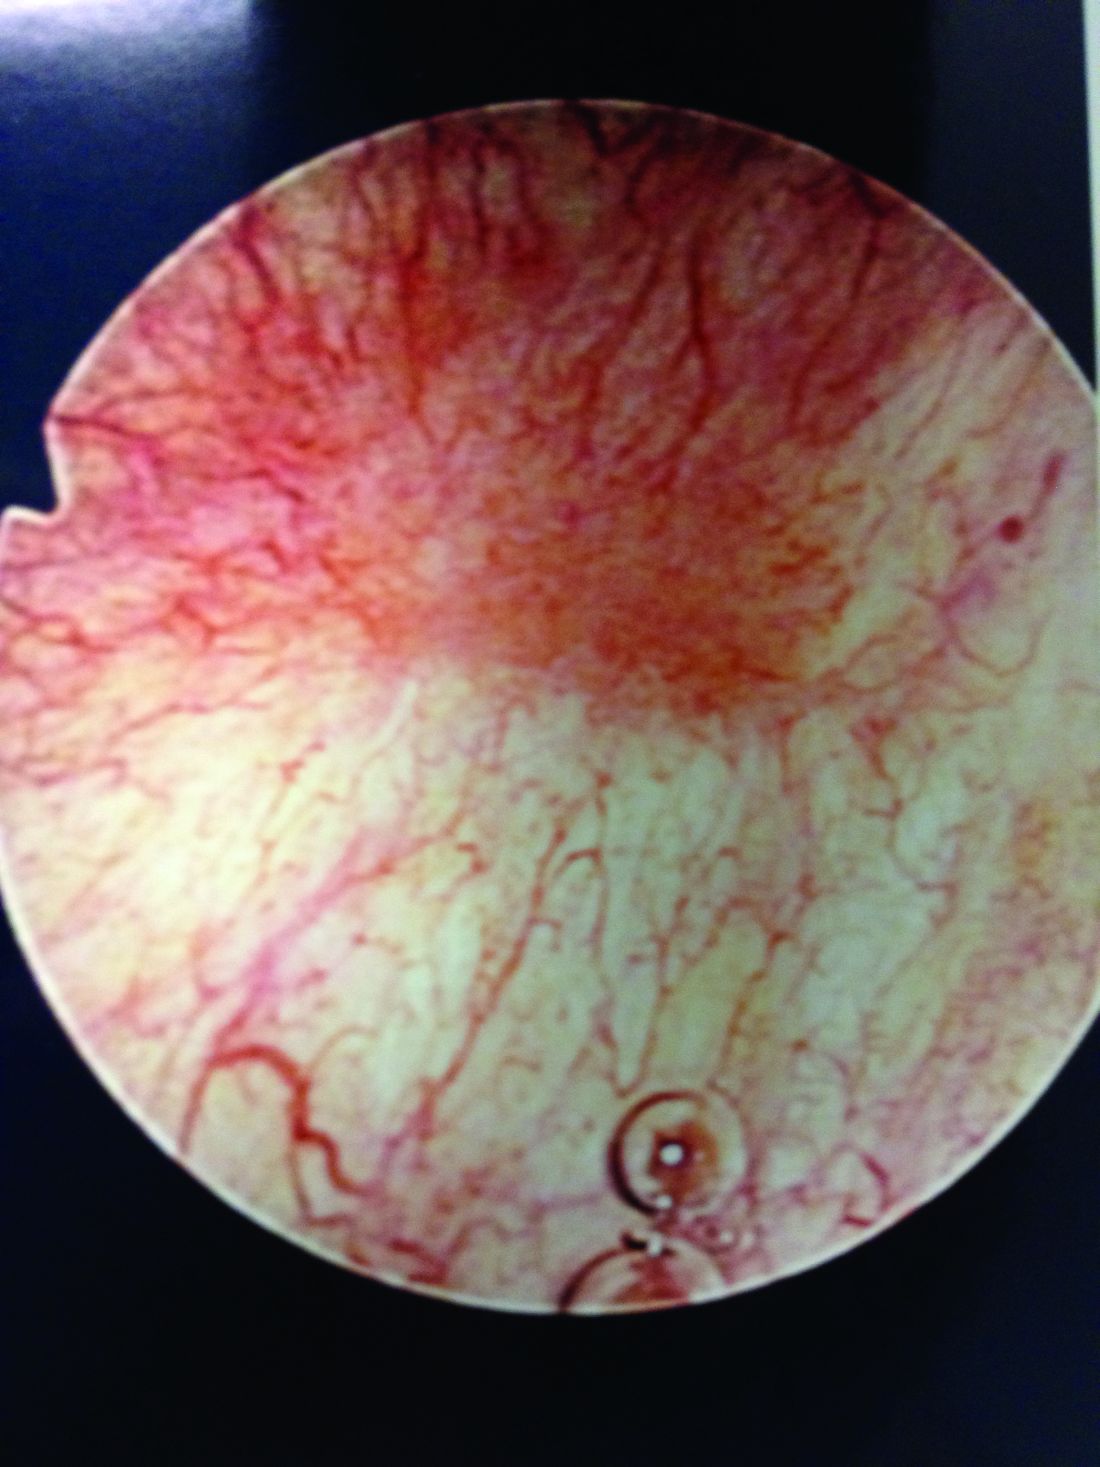

Patients with Hunner’s lesions have a rapid onset of symptoms, typically are older, and have a visible lesion in their bladder that almost always is on the dome or lateral walls. The lesion is often erythematous with central vascularity and mucosal sloughing.

The image shows a Hunner's lesion with erythema and central vascularity. Courtesy Beaumont Urology

The image shows a Hunner's lesion with erythema and central vascularity.